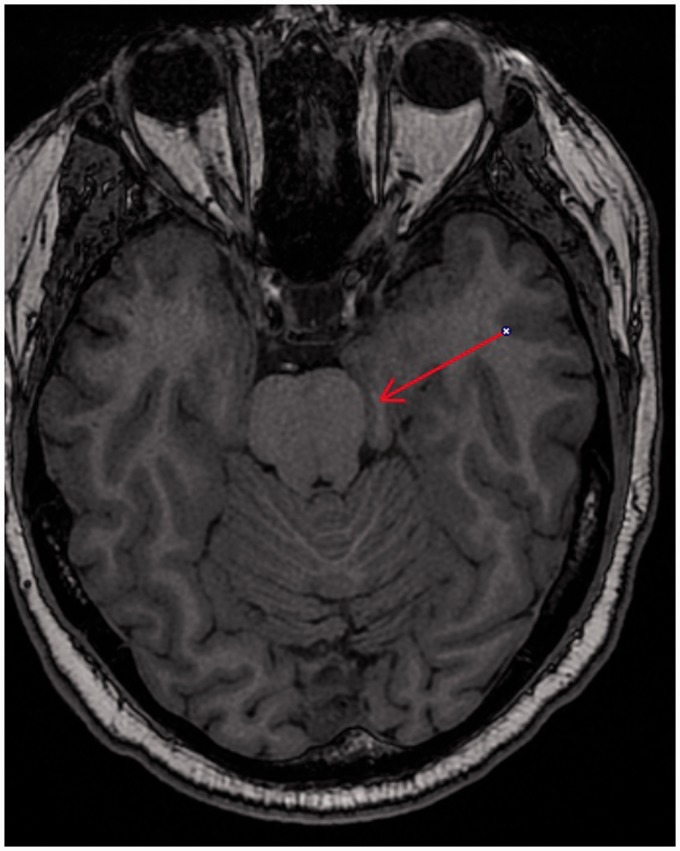

Idiopathic herniation of uncus and parahippocampal gyrus into the ambient cistern is a very rare entity, which could be mistaken for other pathology such as tumor. To the best of our knowledge, two prior cases of this kind of herniation have been described. One of these cases was with associated symptomatology and other abnormalities, and the other was characterized as idiopathic. In this case report, we report a case of accidental finding of a herniation of uncus and parahippocampal gyrus into the ambient cistern, without any other accompanying abnormalities, well depicted by magnetic resonance imaging without further necessity for surgical brain intervention.